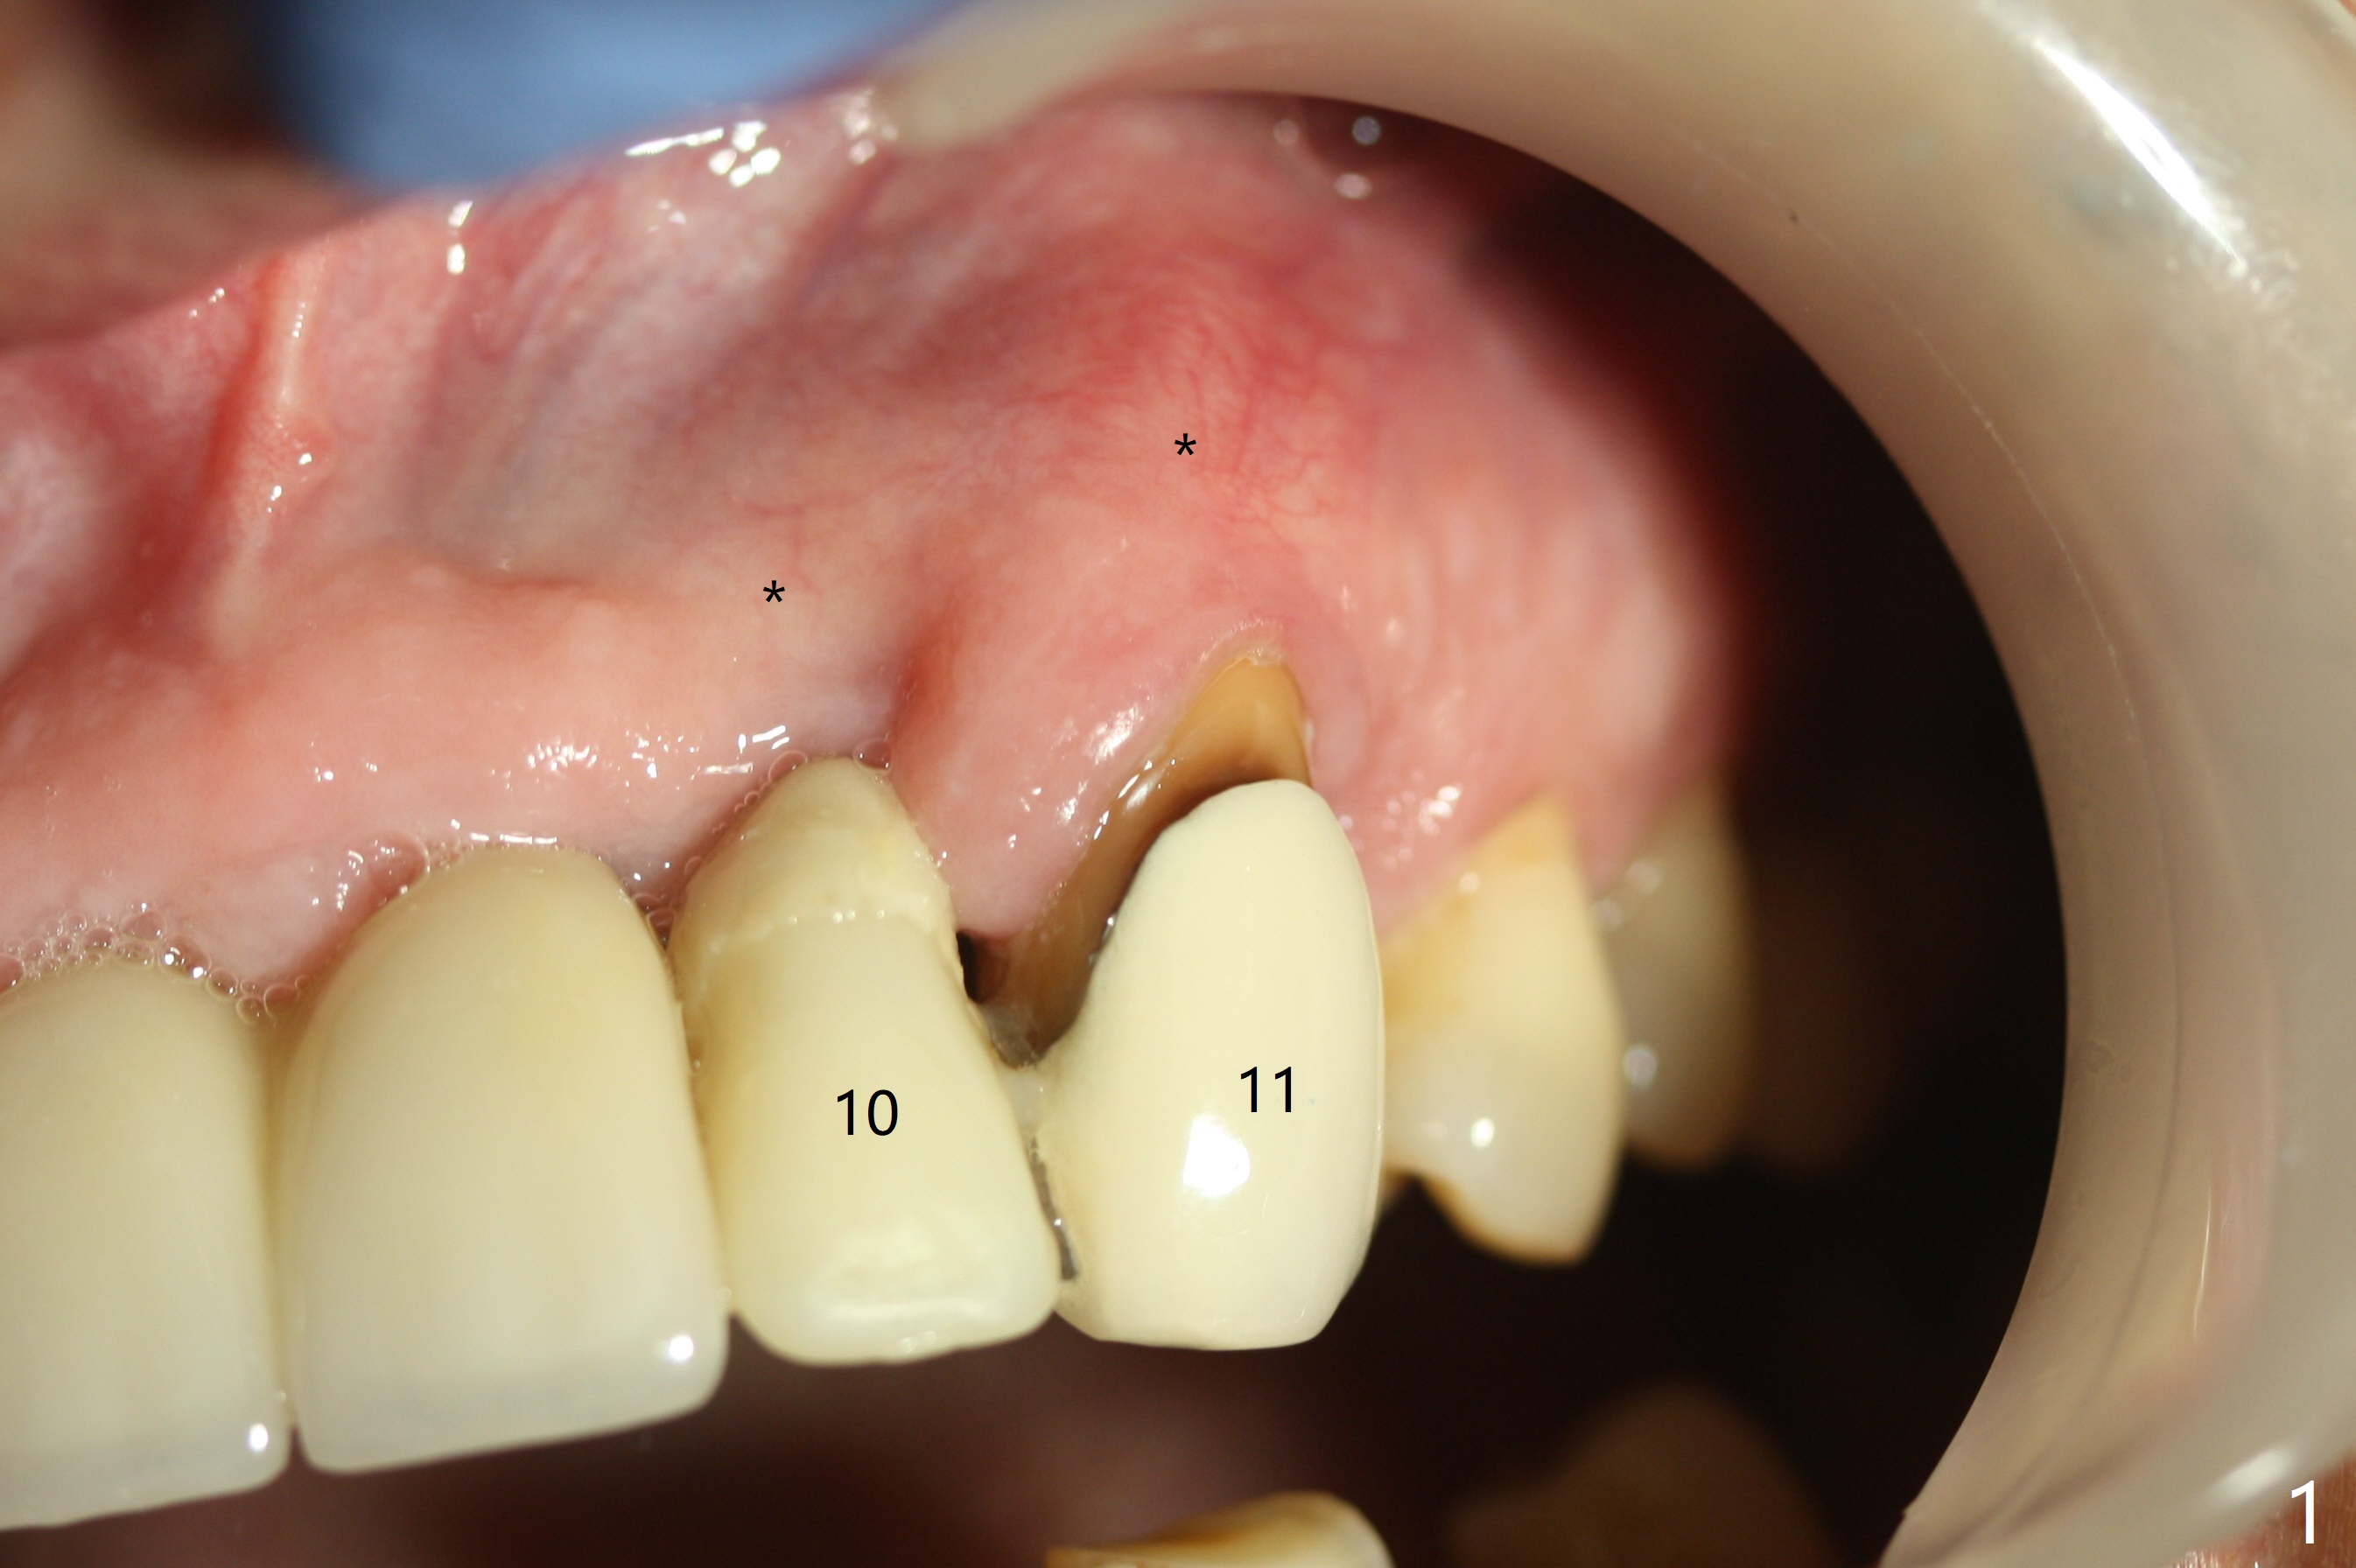

The buccal plate at #10 undergoes atrophy 9 months post immediate implant (Fig.1 *). To prevent the same post-extraction complication at #11, a technique called socket shield is going to be adopted. The buccal portion of the root (Fig.2-6 R, half-moon shaped) remains in place while a 3.5x13 mm implant is placed in the palatal portion of the socket (>50 Ncm). In fact the root is trimmed slightly subcrestal (Fig.6 C). It is assumed that there will be no or minimal bone resorption as long as the periosteum between the buccal plate and the remaining buccal root is not disturbed after tooth removal. After placement of a 4.5x15 degrees A (2mm) angled abutment and Vanilla graft (Fig.7 *), an immediate provisional is fabricated (using a central incisor crown form for #10 because of extra wide space of #11, Fig.8). There is no buccal plate atrophy at the canine 11 days postop (Fig.9). There is smooth transition from the grafted bone to the native bone 4.5 months postop (Fig.10). The buccal plate remains non-atrophic at the canine 4.5 months postop (Fig.11,12). CT taken 1 month post cementation shows that the implants at #10 and 11 are placed somewhat lingually (Fig.13,14 L (*: socket shield)). Gingival swelling is noted (Fig.15 *) with +Bleeding On Probing (^) 8 months post cementation (at the time of #21/24 impression). It appears that the socket shield (Fig.16 S) causes infection and loss of bone graft (*). The shield will be removed with an oblique accessory incision to save the papilla between #10 and 11 (Fig.17 black line). Prepare PRF for sticky bone (x1).